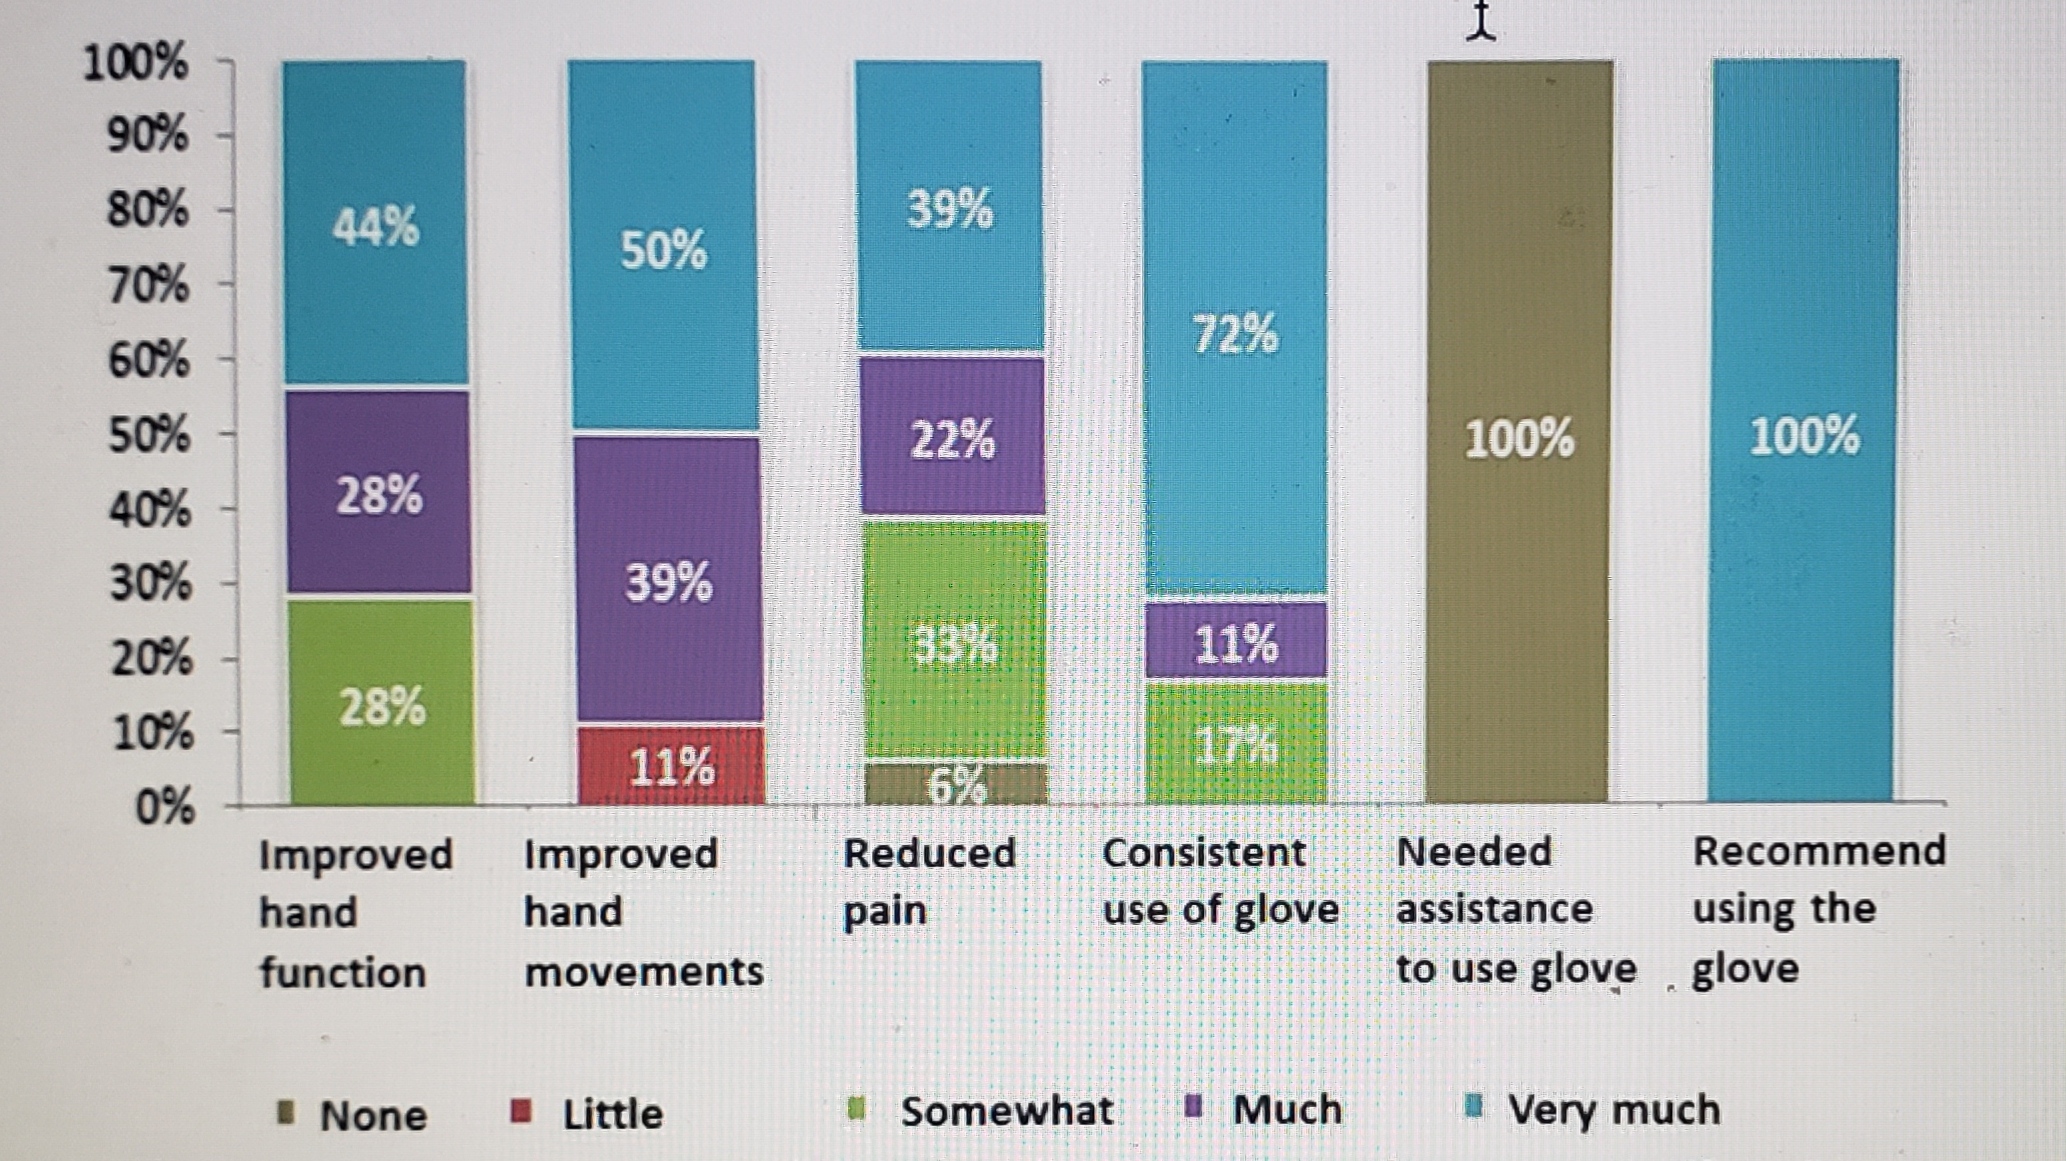

使用压缩手套治疗桡骨远端骨折

使用压缩手套治疗桡骨远端骨折 Miller-Shahabar, I.、Schreuer, N.、Katsevman, H.、Bernfeld, B.、Cons, A.、Raisman, Y. 和 Milman, U. (2018)。功效...